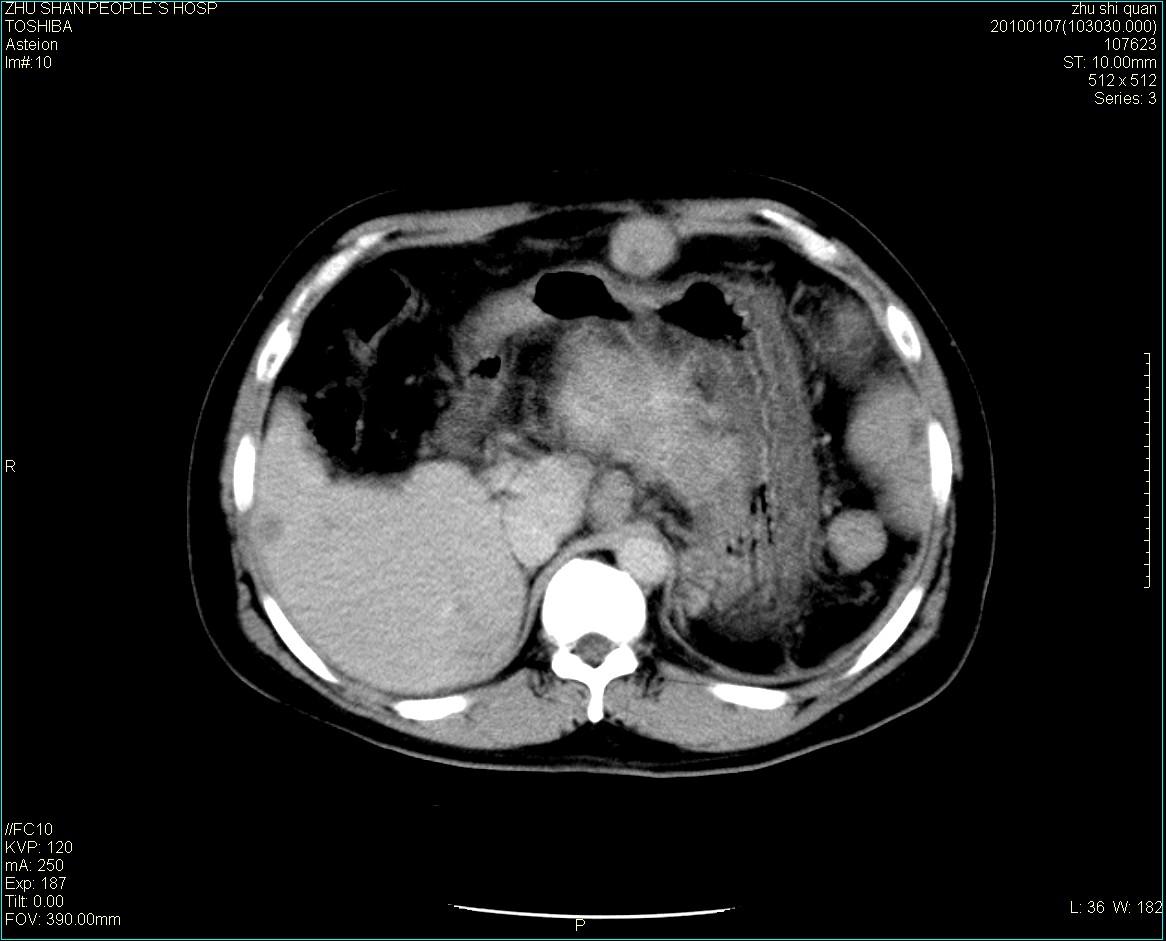

男性病人 肝ca两次术后,今日复查。

多发转移

肝、脾多发转移灶,胸腔积液

1)肝癌并多发性转移。2)双侧胸腔积液(以左侧为甚)伴左下部分肺萎陷。

肝癌术后复发,考虑肝、脾多发转移。

肝癌术后复发,肝内、脾脏、腹膜后及腹膜多发转移,腹水,双侧胸腔积液(以左侧为甚)伴左下膨胀不全。

肝、脾多发转移灶,胸腔积液。

肝癌术后复发,肝内、脾脏、腹膜后及腹膜多发淋巴结转移,腹水,双侧胸腔积液。